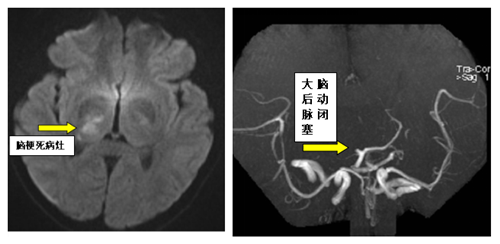

该患者急诊到我院后,急诊分诊考虑为急性脑卒中,立即进入卒中绿色通道,急诊CT排除脑出血,急诊MRI考虑右侧丘脑、枕叶急性脑梗死,并发现患者右侧大脑后动脉闭塞。

患者检查医学影像资料

争分夺秒,与患者及家属沟通后立即行脑血管造影检查,明确患者病因为右侧椎动脉内膜撕裂,形成动脉夹层,夹层内血栓脱落栓塞右侧大脑后动脉,从而导致急性脑梗死。